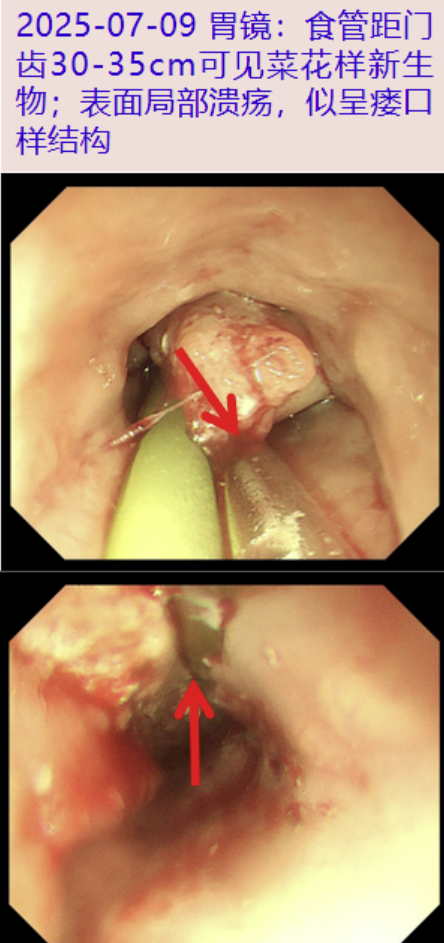

2025-07-09 复查胃镜: 食管距门齿30-35cm可见菜花样新生物,表面糜烂坏死,质地脆,部位包绕小肠营养管, 表面局部溃疡,似呈瘘口样结构,异物钳探查窦道较短,触碰后质地脆,易出血,无法留置引流管于窦道深部。

2025-07-10 食管活检组织初步病理: 鳞状上皮重度异型增生,癌变(鳞状细胞癌,分化II级)。

老年男性,主要表现为发热、咳嗽、咳脓痰、咯血,亚急性病程,既往脑出血病史,追问病史患者曾有醉酒史,查白细胞、粒细胞及炎症指标升高,CT示右下肺脓肿,食管瘘机会大,食管中下段管壁增厚。查痰培养及痰mNGS:肺炎克雷伯菌,完善胃镜、气管镜示食管黏膜缺损,因患者咳嗽剧烈未行活检。经抗感染治疗患者病情反复迁延,复查CT示右肺多发炎症,右下肺脓肿及食管瘘伴周围脓肿较前进展;再次完善胃镜见食管距门齿30-35cm可见菜花样新生物,最终食管活组织病理诊断为食管鳞癌。回顾本患者病情演变过程,患者以食管癌起病,肿瘤侵袭性生长最终侵犯食管外膜,形成食管瘘口,并累及纵隔、肺部等周围组织,进一步形成肺脓肿及纵隔脓肿。

患者第2次因发热、咳嗽咳痰、气促入院,复查胸部CT示右肺多发炎症,右下肺脓肿较2025-06-05明显进展,且形成食管瘘纵隔脓肿。患者经抗感染治疗效果不佳,分析病因,考虑肺脓肿感染蔓延致食管瘘可能性较小,因此,为明确病因再次行胃镜示食管距门齿30-35cm可见菜花样新生物,表面糜烂坏死,质地脆,部位包绕小肠营养管,表面局部溃疡,似呈瘘口样结构;本次胃镜经抗感染治疗后脓苔较前明显减少,黏膜水肿减轻,最终经活检后明确诊断为食管鳞癌。